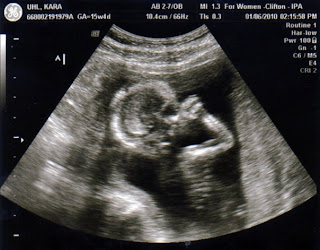

15 week ultrasound. The timing of the ultrasound is important because the test involves measuring the fluid at the back of the baby's neck. For the first time, her head is smaller than her body, marking another developmental milestone. The large bones that make up her skull are forming and.

But by week 15, your baby could be the size of a large russet potato --around 6 inches long. If you have a 4-month prenatal appointment scheduled for this week, you could be getting a 16-week ultrasound. Week 15 Ultrasound In this 3-D image, the baby-to-be is curled up, her hands covering her face (she's about the size of a grapefruit).

15 Weeks Pregnant Ultrasound You probably can't feel it yet, but a 15 weeks pregnant ultrasound would reveal that baby's squirming a ton in there, now that they’re able to move all their limbs and joints!. Once your OB sees a normal 16 weeks pregnant ultrasound, your chance of miscarriage drops to only 1 percent. The fetus can swallow, suck a finger, move the own arms and legs, clench fists.

Find out how she's starting to use her muscles and what important tests you should take at this stage of pregnancy. At this period, we can finally see the external sexual organs of the future baby. During the pregnancy week 15 ultrasound, the baby is around 4 inches in length and weighs in at around 2.4 ounces and is continuing to grow.